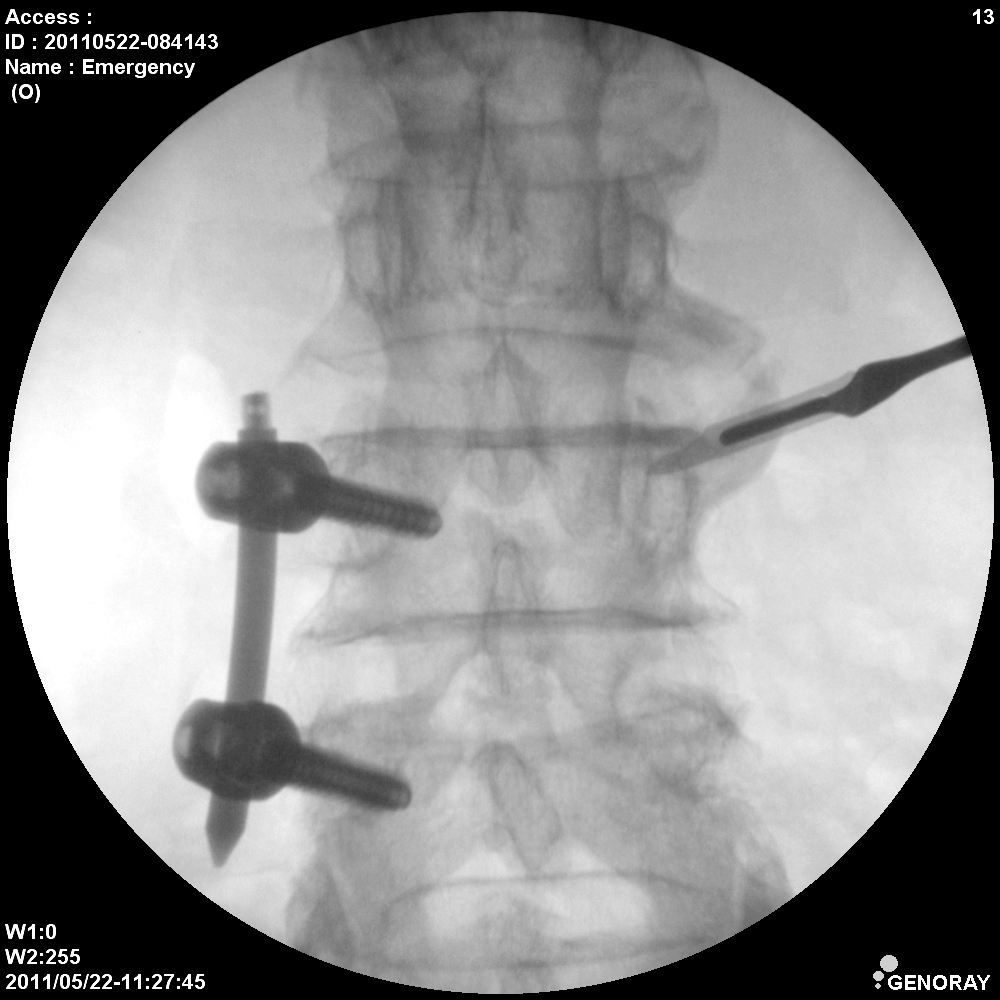

Аппарат применяется в различных областях медицины, таких как хирургия, ортопедия, педиатрия, травматология, урология и многих других. «АРХМ-РЕНЕКС» имеет широкий диапазон перемещений, легко позиционируется во всех направлениях, а так же имеет не большие габариты и вес обеспечивающие маневренность и простоту перемещений.

В качестве приемника используется усилитель рентгеновского изображения (УРИ) с ПЗС-матрицей 1024х1024 пикселей. Мощность рентгеновского питающего устройства 2,2 кВт.

- Непрерывная и импульсная рентгеноскопия с цифровой обработкой изображения.

- Цифровая рентгенография.